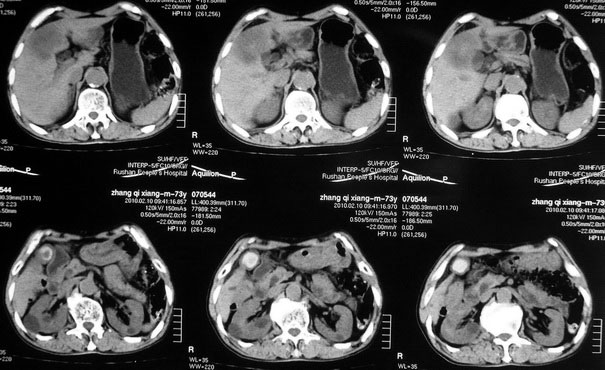

肝胆管细胞癌

患者AFP正常,无肝病病史。CA199 1000ng/ml,CEA偏高。血象WBC正常,N偏高。

这个病人是有病理的,做了肝活检,初八出结果。

化脓性胆囊炎累及肝脏;胆管细胞癌;肝转移瘤

活检病理

:是

胆管细胞癌

这个病人开始就是主要鉴别的肝脓肿和胆管细胞癌。可是增强后环征也不明显,占位内造影也非常不明显。这种情况怎么判断?谢谢大家。

病灶强化幅度较轻,低密度坏死区内见无定形高密度影,是其特点。